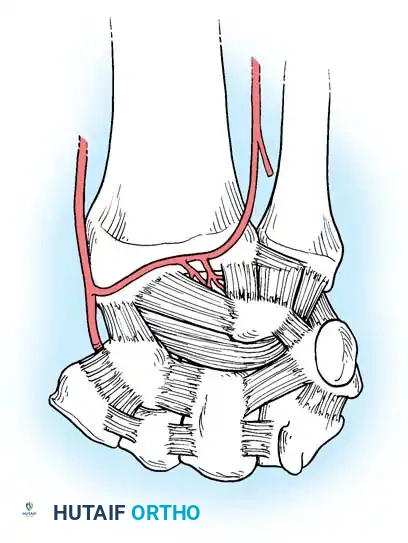

Vascular Anatomy of the Carpus

Understanding the extraosseous and intraosseous vascularity of the wrist is paramount, particularly when managing fractures of the scaphoid and lunate, which are highly susceptible to avascular necrosis (AVN).

Gelberman et al. mapped the terminal branches of the radial, ulnar, and anterior interosseous arteries, which form three dorsal and three palmar transverse arterial arches.

Dorsal Arterial Arches

- Dorsal Radiocarpal Arch: Supplies the proximal lunate and triquetrum.

- Dorsal Intercarpal Arch: The largest arch, supplying the distal carpal row and providing anastomotic flow to the lunate and triquetrum.

- Basal Metacarpal Arch: Supplies the distal carpal row and metacarpal bases.

Palmar Arterial Arches

- Palmar Radiocarpal Arch: Supplies the palmar lunate and triquetrum.

- Palmar Intercarpal Arch: Highly variable; rarely contributes nutrient vessels to the carpus.

- Deep Palmar Arch: Consistent arch communicating with the dorsal basal metacarpal arch.

Surgical Warning: The scaphoid receives 70-80% of its blood supply from branches of the radial artery entering the dorsal ridge, perfusing the bone in a retrograde fashion. Fractures at the scaphoid waist or proximal pole disrupt this delicate supply, leading to high rates of nonunion and AVN. Surgical approaches must meticulously preserve the dorsal ridge vasculature.